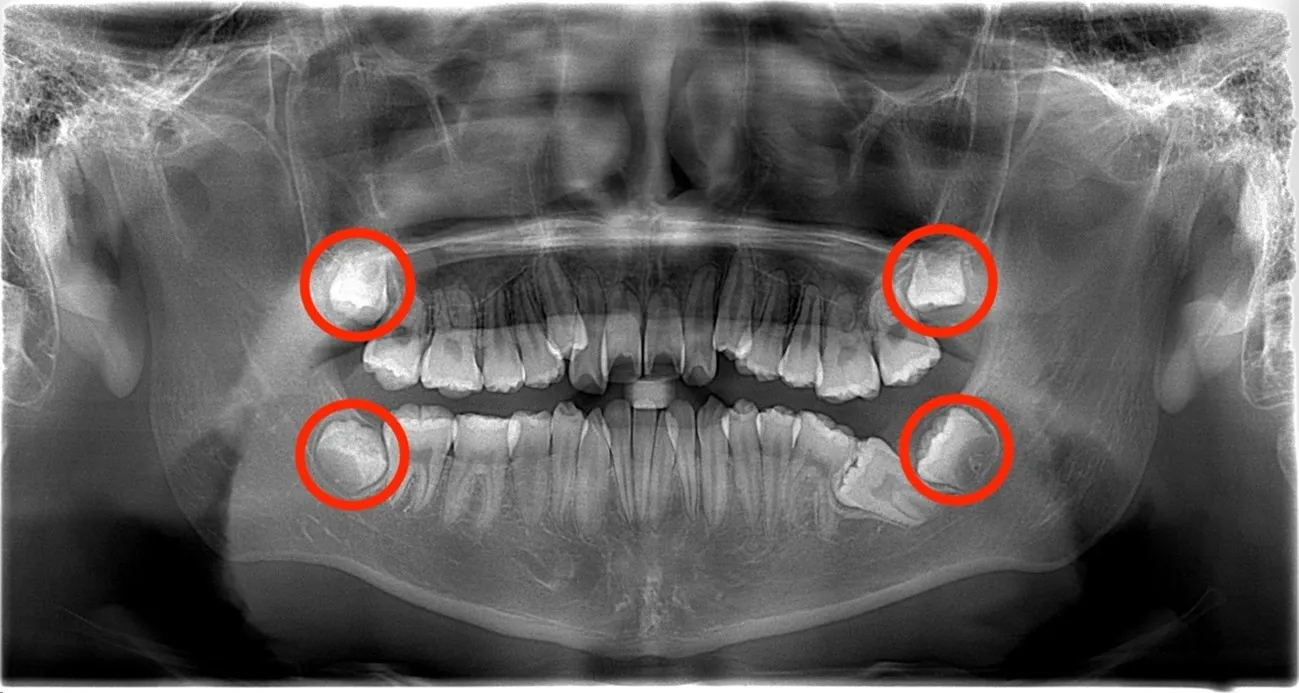

歯胚抜歯の時期を逸した為に歯列不正になってしまった症例

歯胚抜歯の適切な時期を逃してしまったことで、歯列不正へとつながった症例です。画像では、左下の第二大臼歯(7番)が横向きのまま埋伏しており、本来の位置に正常に生えてくることができない状態になっています。このような埋伏は、隣接する親知らず(8番)の萌出方向や、顎の骨の大きさ・形態の影響により歯が生えるためのスペースが不足した際に起こりやすいとされています。歯胚の段階で早期に異常を確認できていれば、歯列不正や咬み合わせへの悪影響を未然に防げた可能性が高く、“適切な時期での診断と対応の重要性”を示す典型的なケースです。